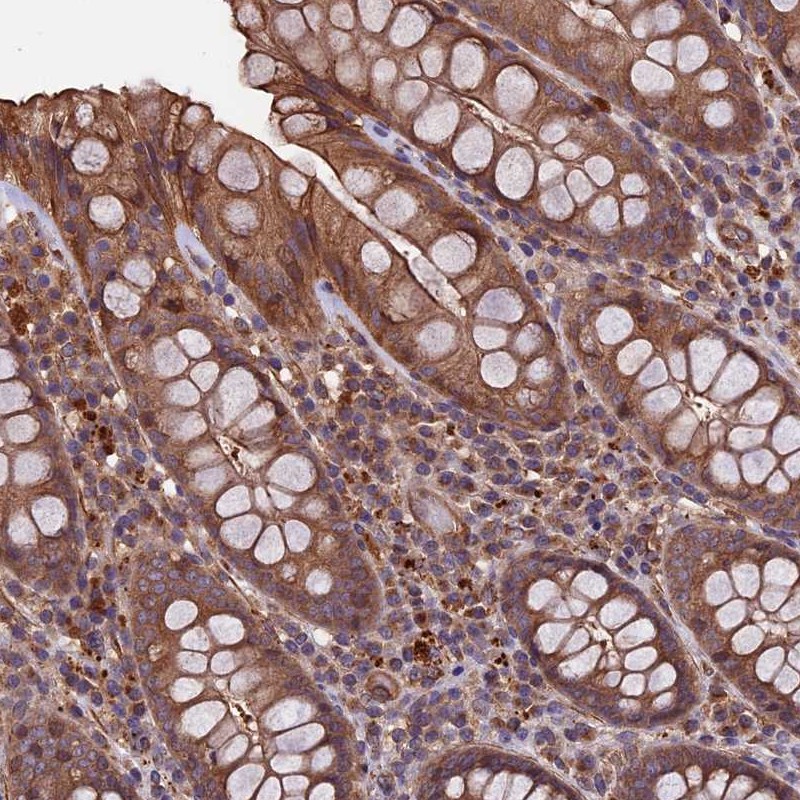

Immunohistochemical staining of human rectum shows moderate cytoplasmic and membranous positivity in glandular cells.